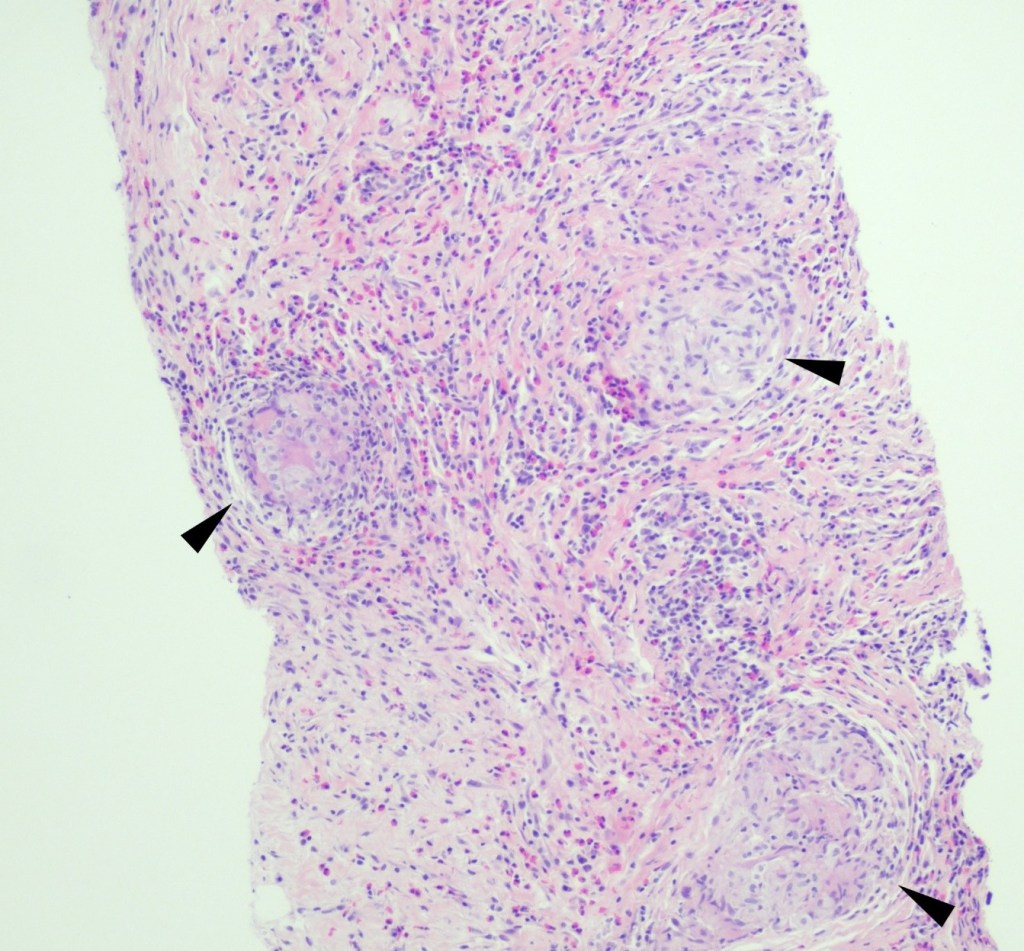

Neurosurgery evacuated 17 mL of fluid from the mass and a ventricular drain was placed. Gram stain of the evacuated fluid identified many white blood cells and few gram-positive cocci in pairs, chains and clusters (Figure 3). Postoperatively, the patient was mechanically ventilated and medicines were used to support his blood pressure in the ICU. Broad-spectrum antibiotics were continued for CNS penetration and activity against possible oral flora.

Figure 3. Representative Gram stain of the pus drained from the abscess. Multiple couplets of lancet-shaped gram positive organisms identified. Slight halo around the bacteria suggests the presence of a capsule.

A 59 year old female presented with a one-month history of generalized abdominal pain, difficulty breathing, and early satiety. She was previously seen at an external facility and found to have liver hypointensity and abdominal distension which were concerning for liver cancer. Social history included travel to Sacramento and California deserts for hiking in the last few months. CT of the abdomen and pelvis demonstrated extensive peritoneal carcinomatosis with no primary etiology and a right hepatic lobe focus. MRI revealed diffuse omental caking and peritoneal thickening consistent with peritoneal carcinomatosis. Hepatic lesions also seen on MRI were consistent with hemangiomas. Laboratory evaluation was positive for Hepatitis B virus infection along with elevated liver enzymes (AST and ALT), CA-125, and normal levels of CEA. Paracentesis was performed removing 3 liters of yellow, cloudy fluid. Cytology demonstrated benign mesothelial cells, macrophages, and mixed inflammatory cells with a lymphocytic predominance in the peritoneal fluid. No malignant cells were identified. Initial aerobic, anaerobic, mycobacterial, and fungal cultures were negative. Serum Cryptococcus neoformans antigen testing was also negative. Ultrasound-guided core biopsy of the omental mass was performed; however, tissue was not sent for culture. Histopathology revealed granulomatous inflammation with eosinophilic infiltrate (Figure 1). A singular spherule was highlighted by GMS stain (Figure 2).  Fungal serology via complement fixation for Coccidioides was positive (titer: 1:8) while Blastomyces, Histoplasma, and Aspergillus serologies were negative. The patient was subsequently managed on fluconazole.

Figure 1. Core biopsy of omental tissue revealing granulomatous inflammation and diffuse eosinophilic infiltrate in a background of chronic inflammation, lymphocytes and fibrosis. Arrows indicate granuloma formation (H&E, 100x).